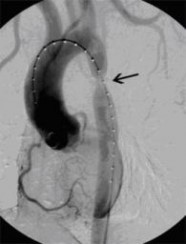

Aortenkoarktationsstenose vor Stentimplantation (Bild 1 von 4) Vorwärts »

« Zurück Aortenkoarktationsstenose nach Stentimplantation (Bild 2 von 4) Vorwärts »